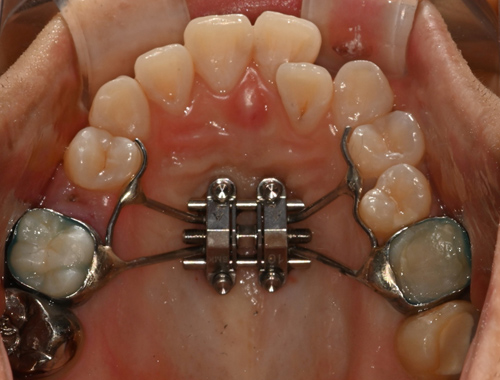

확장 후